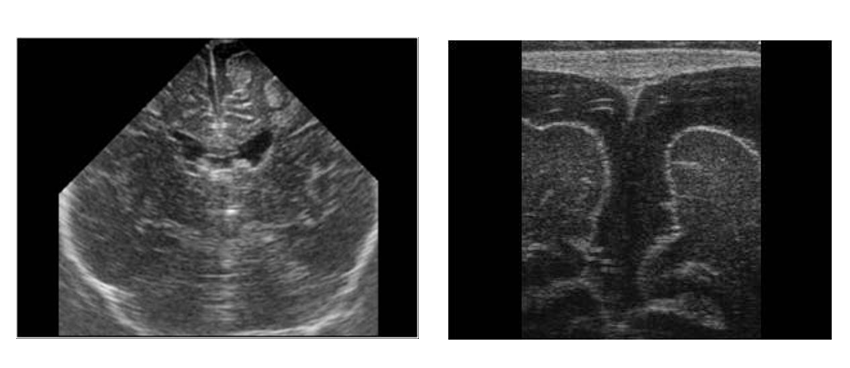

Kỹ thuật siêu âm qua thóp được thực hiện bằng cách đặt một thiết bị gọi là máy siêu âm lên bụng của bệnh nhân. Máy sẽ phát ra sóng siêu âm và thu lại sóng phản xạ từ các cơ quan bên trong cơ thể. Những sóng này sẽ được chuyển đổi thành hình ảnh trên màn hình máy tính, giúp bác sĩ xem xét các cơ quan bên trong cơ thể.